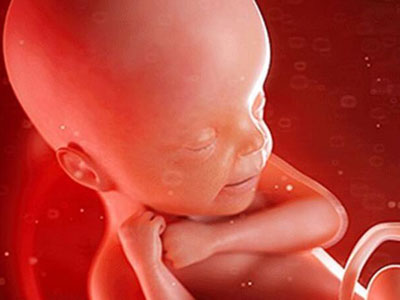

其实孩子还是胎宝宝时,就已经开始各种“搞怪”了,这也是为什么咱们能感受到他们的存在。但如果你以为胎宝宝只会这些就错了,他们在妈妈肚子里干的事情多着呢!

这可是胎宝宝的头等大事!他呢,每天大部分时间都在睡觉。安静型睡眠时,他紧闭双眼,静悄悄的;活动型睡眠时,他睡的比较浅,还会不时伸伸懒腰,动动手脚,有时候一点动静就能惊醒他!另外,胎宝宝还会做梦呢,是不是很神奇?

在还只有小海马那么大时,胎宝宝已经解锁了新技能——游泳。每天醒着的时间里,他喜欢在妈妈的肚子里游来游去,直到最后长大到占满子宫腔时才作罢。

慢慢的,胎宝宝学会打哈欠了,每次差不多5,6秒。这不仅能使面部神经得到放松,还能帮助胎宝宝大脑发育,一举两得!想想那小小的一只打哈欠的模样,心都要融化了!

胎宝宝特别喜欢做吞咽羊水的小游戏,乐在其中。随着胎宝宝长大,吞咽羊水的量逐渐增加,等到快出生时,每天差不多能有500-700ml呢。

打嗝

玩脐带

拳打脚踢

分辨声音

扮鬼脸

发脾气

原来胎宝宝在妈妈肚子里竟有这么多小动作!虽然这些我们有的能感觉到,有的不能,但只要想到此刻宝贝可能在做鬼脸、撅屁股等,然后学到的东西越来越多,孕期的各种不适就都不算什么了。宝贝,快快长大哦,妈妈期待见到你的那天!